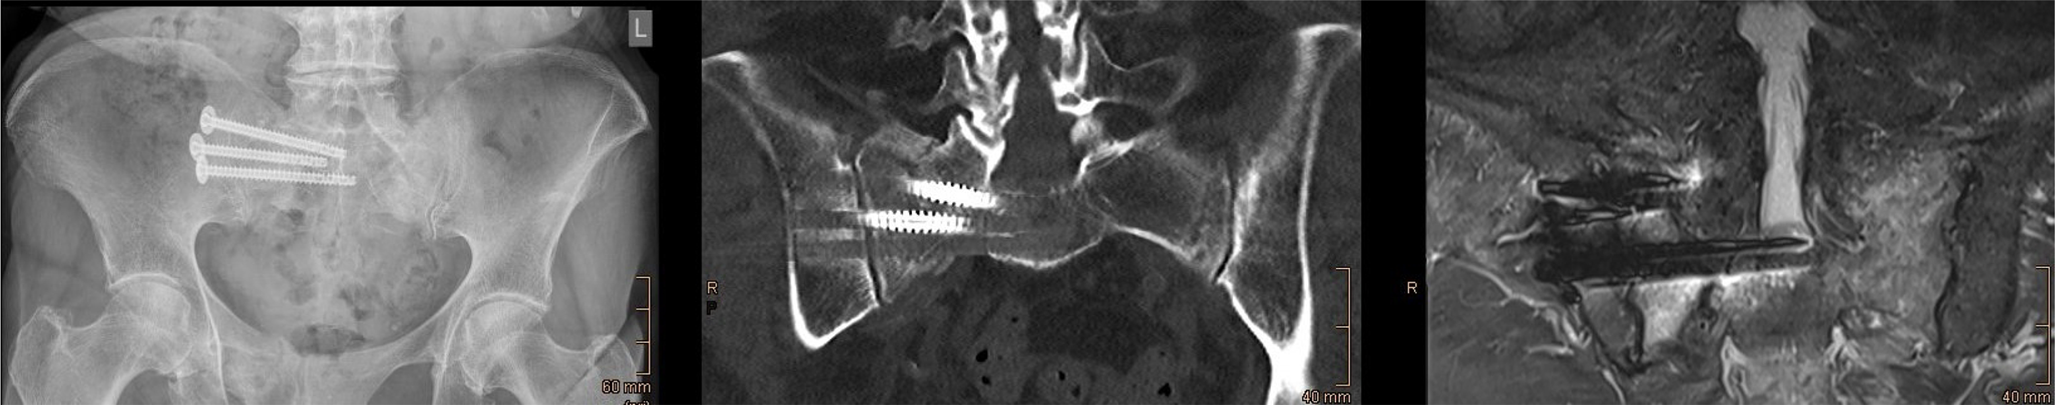

Unilateral sacral fragility fractures: a comparative study of unilateral vs. bilateral minimally invasive osteosynthesis

Unilateral sacral fragility fractures are frequently managed with unilateral percutaneous iliosacral screw fixation, which...